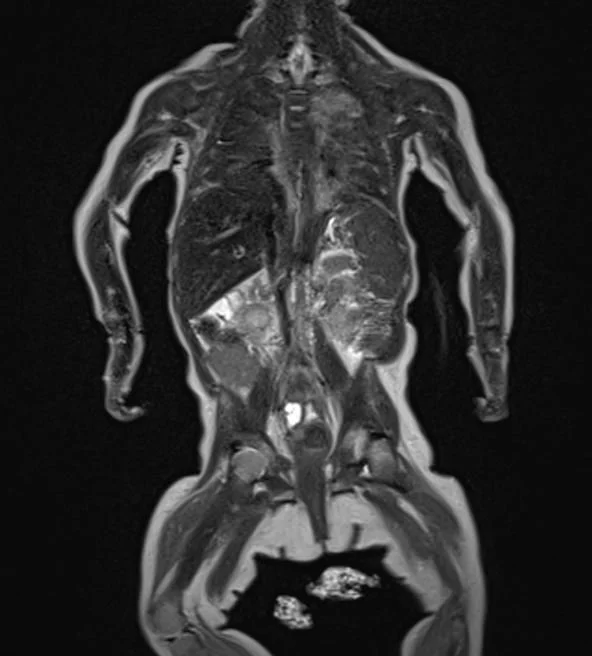

Rare and pediatric disease trials come with complex challenges that require specific expertise and experience. We have the radiology exerts to support the specific requirements of pediatric clinical trials. Many rare diseases affect children, and pediatric trials bring additional challenges.

They require specific protocols, involve additional regulations and demand expertise and experience. BICL’s experts are experienced in oncology, MSK and other pediatric disorders including growth plate disturbance, bone age and osteochondroma.